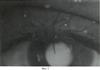

Пациентка Н. 75 лет.

Диагноз: Новообразование кожи левого верхнего века. (Фиг.4).

Пациенту перорально дают препарат «Аласенс» в дозе 15 мг/кг веса, растворяя его в обычной воде. Через 3 часа после введения препарата пациента усаживают перед экраном из высокопоглащающей ткани. С помощью 2 люминесцентных ламп с максимумами излучения 390, 415 и 433 нм, укрепленных на кронштейнах, добиваются максимально равномерного освещения возбуждающим излучением зоны новообразования. Производят регистрацию интересующего участка цифровой камерой с RGB CCD-матрицей. На полученном трехканальном изображении (Фиг.5) с помощью программы для ЭВМ CancerPlot оценивают долю участия красного канала, соответствующего флуоресценции протопорфирина-IX (Фиг.6). Доля участия красного канала в флуоресцентном изображении интрадермального невуса (Rtum) составила 33.87%. Доля участия красного канала в флуоресцентном изображении окружающей кожи (Rcut) составила 27.89%.

Rdiff=((33.87-27.89)/27.89)·100%=21.4%

Колориметрический отход по R-каналу на флуоресцентном изображении новообразования составил +21.4%, что больше +10%. Полученный результат говорит в пользу злокачественного характера опухоли. Гистологический диагноз (базально-клеточный рак кожи) подтвердил злокачественный характер новообразования.